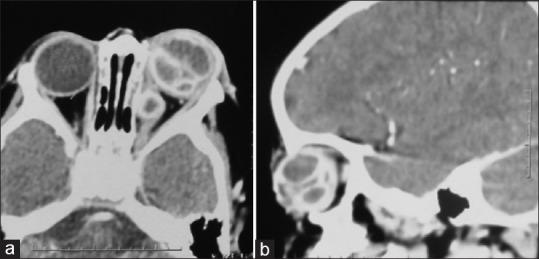

is a rare cause of endophthalmitis in immunocompetent individuals with poor visual outcomes. We, herein report a 15 month otherwise healthy child, who presented with hyphema, vitreous hemorrhage and secondary glaucoma following a vague history of trauma in the left eye 2 months before presentation. He presented a week later with features of panophthalmitis which were confirmed on B-scan and orbital CT scan. CT scan with contrast revealed the presence of multiple ring enhancing abscesses in the vitreous cavity and also in the intraconal space. Evisceration was done and smear and cultures revealed . Rare presentation in a healthy pediatric patient and typical CT scan findings are discussed.

在免疫功能正常的个体中,是导致眼内炎的罕见原因,视力预后较差。在此,我们报告一名15个月大的健康儿童,其在就诊前2个月左眼有模糊的外伤史,之后出现前房积血、玻璃体积血和继发性青光眼。一周后他因全眼球炎症状前来就诊,B超和眼眶CT扫描证实了这一情况。增强CT扫描显示玻璃体腔和肌锥内间隙存在多个环形强化脓肿。进行了眼球摘除术,涂片和培养结果显示……讨论了健康儿科患者中的罕见表现及典型的CT扫描结果。